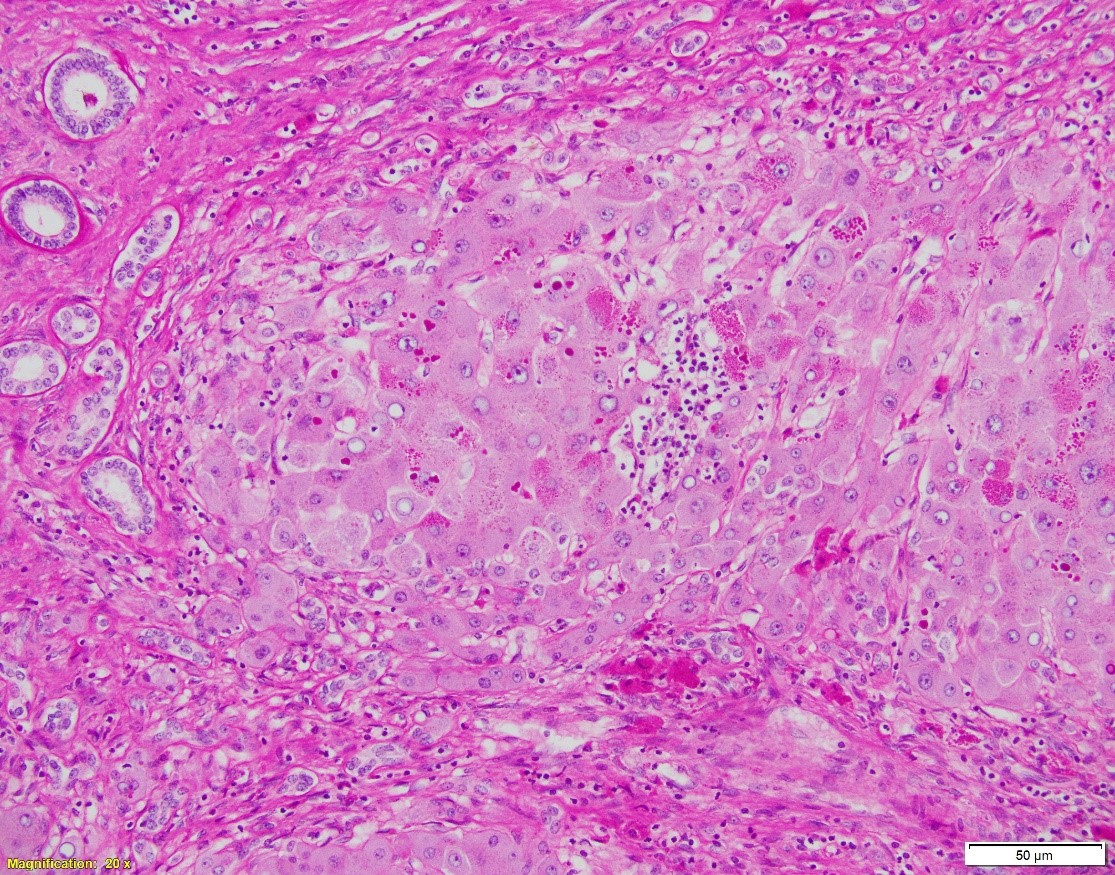

Patient is a 66-year-old female with NASH cirrhosis s/p OLT. Specimen: native liver explant. Pictures:

A. Hematoxylin and eosin, 20x. B. Hematoxylin and eosin, 100x. C. PAS w/diastase, 40x

- The intracytoplasmic globules positive on both PAS w/ and w/o diastase

In cirrhotic liver removed for transplantation, A1-antitrypsin deficiency grossly presents as micronodular or mixed micro- and macronodular pattern of cirrhosis. Microscopic findings include intracytoplasmic eosinophilic globules in periportal hepatocytes, which does not always correlate with the clinical liver disease. PAS w/diastase is helpful to distinguish A1-antitrypsin globules from glycogen. In infants, the globules may be absent or hard to detect; in these children, however, the disease may present as liver injury in form of neonatal hepatitis, cholestatic hepatitis, or extrahepatic biliary atresia, with variable degrees of fibrosis. In adults, besides the presence of A1AT globules, the changes may include mild portal inflammation and bile ductular proliferation, mild steatosis, and variable fibrosis.